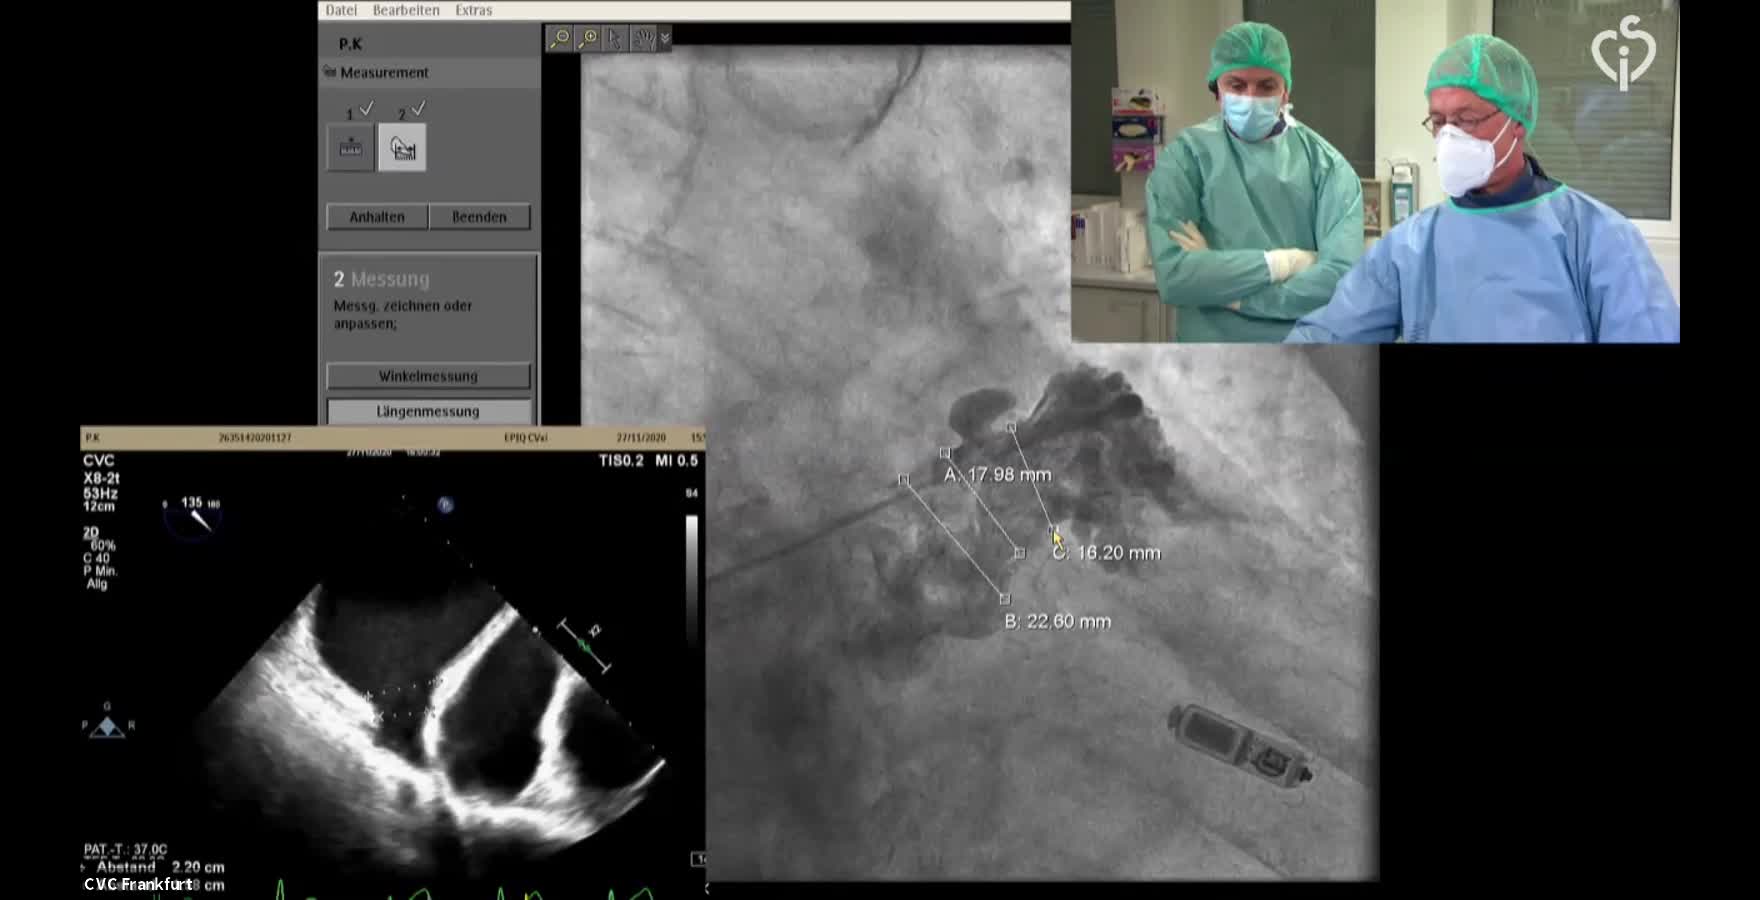

CSI CATHLAB LIVE - INTER-ATRIAL SHUNT FOR DECOMPRESSION OF THE LEFT ATRIUM IN A PATIENT WITH VERY SEVERE HEART FAILURE WITH THE AFR DEVICE